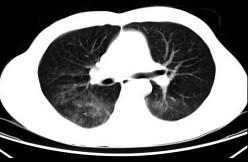

男,35岁,被车撞伤后1小时,结合影像图像选择其最可能的诊断为 ( )A、肺挫伤B、支气管扩张C、肺结核D、间质性肺炎E、肺炎

问题 男,35岁,被车撞伤后1小时,结合影像图像选择其最可能的诊断为 ( )

选项 A、肺挫伤 B、支气管扩张 C、肺结核 D、间质性肺炎 E、肺炎

答案 A